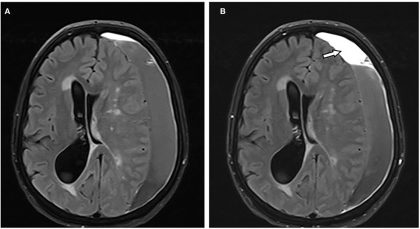

Kesehatan | • September 16, 2025 • Hematoma Subdural: Penyebab, Gejala, Jenis dan Pengobatan Subdural hematoma adalah kondisi medis yang serius dan memerlukan penanganan segera. Kondisi ini terjadi ketika...